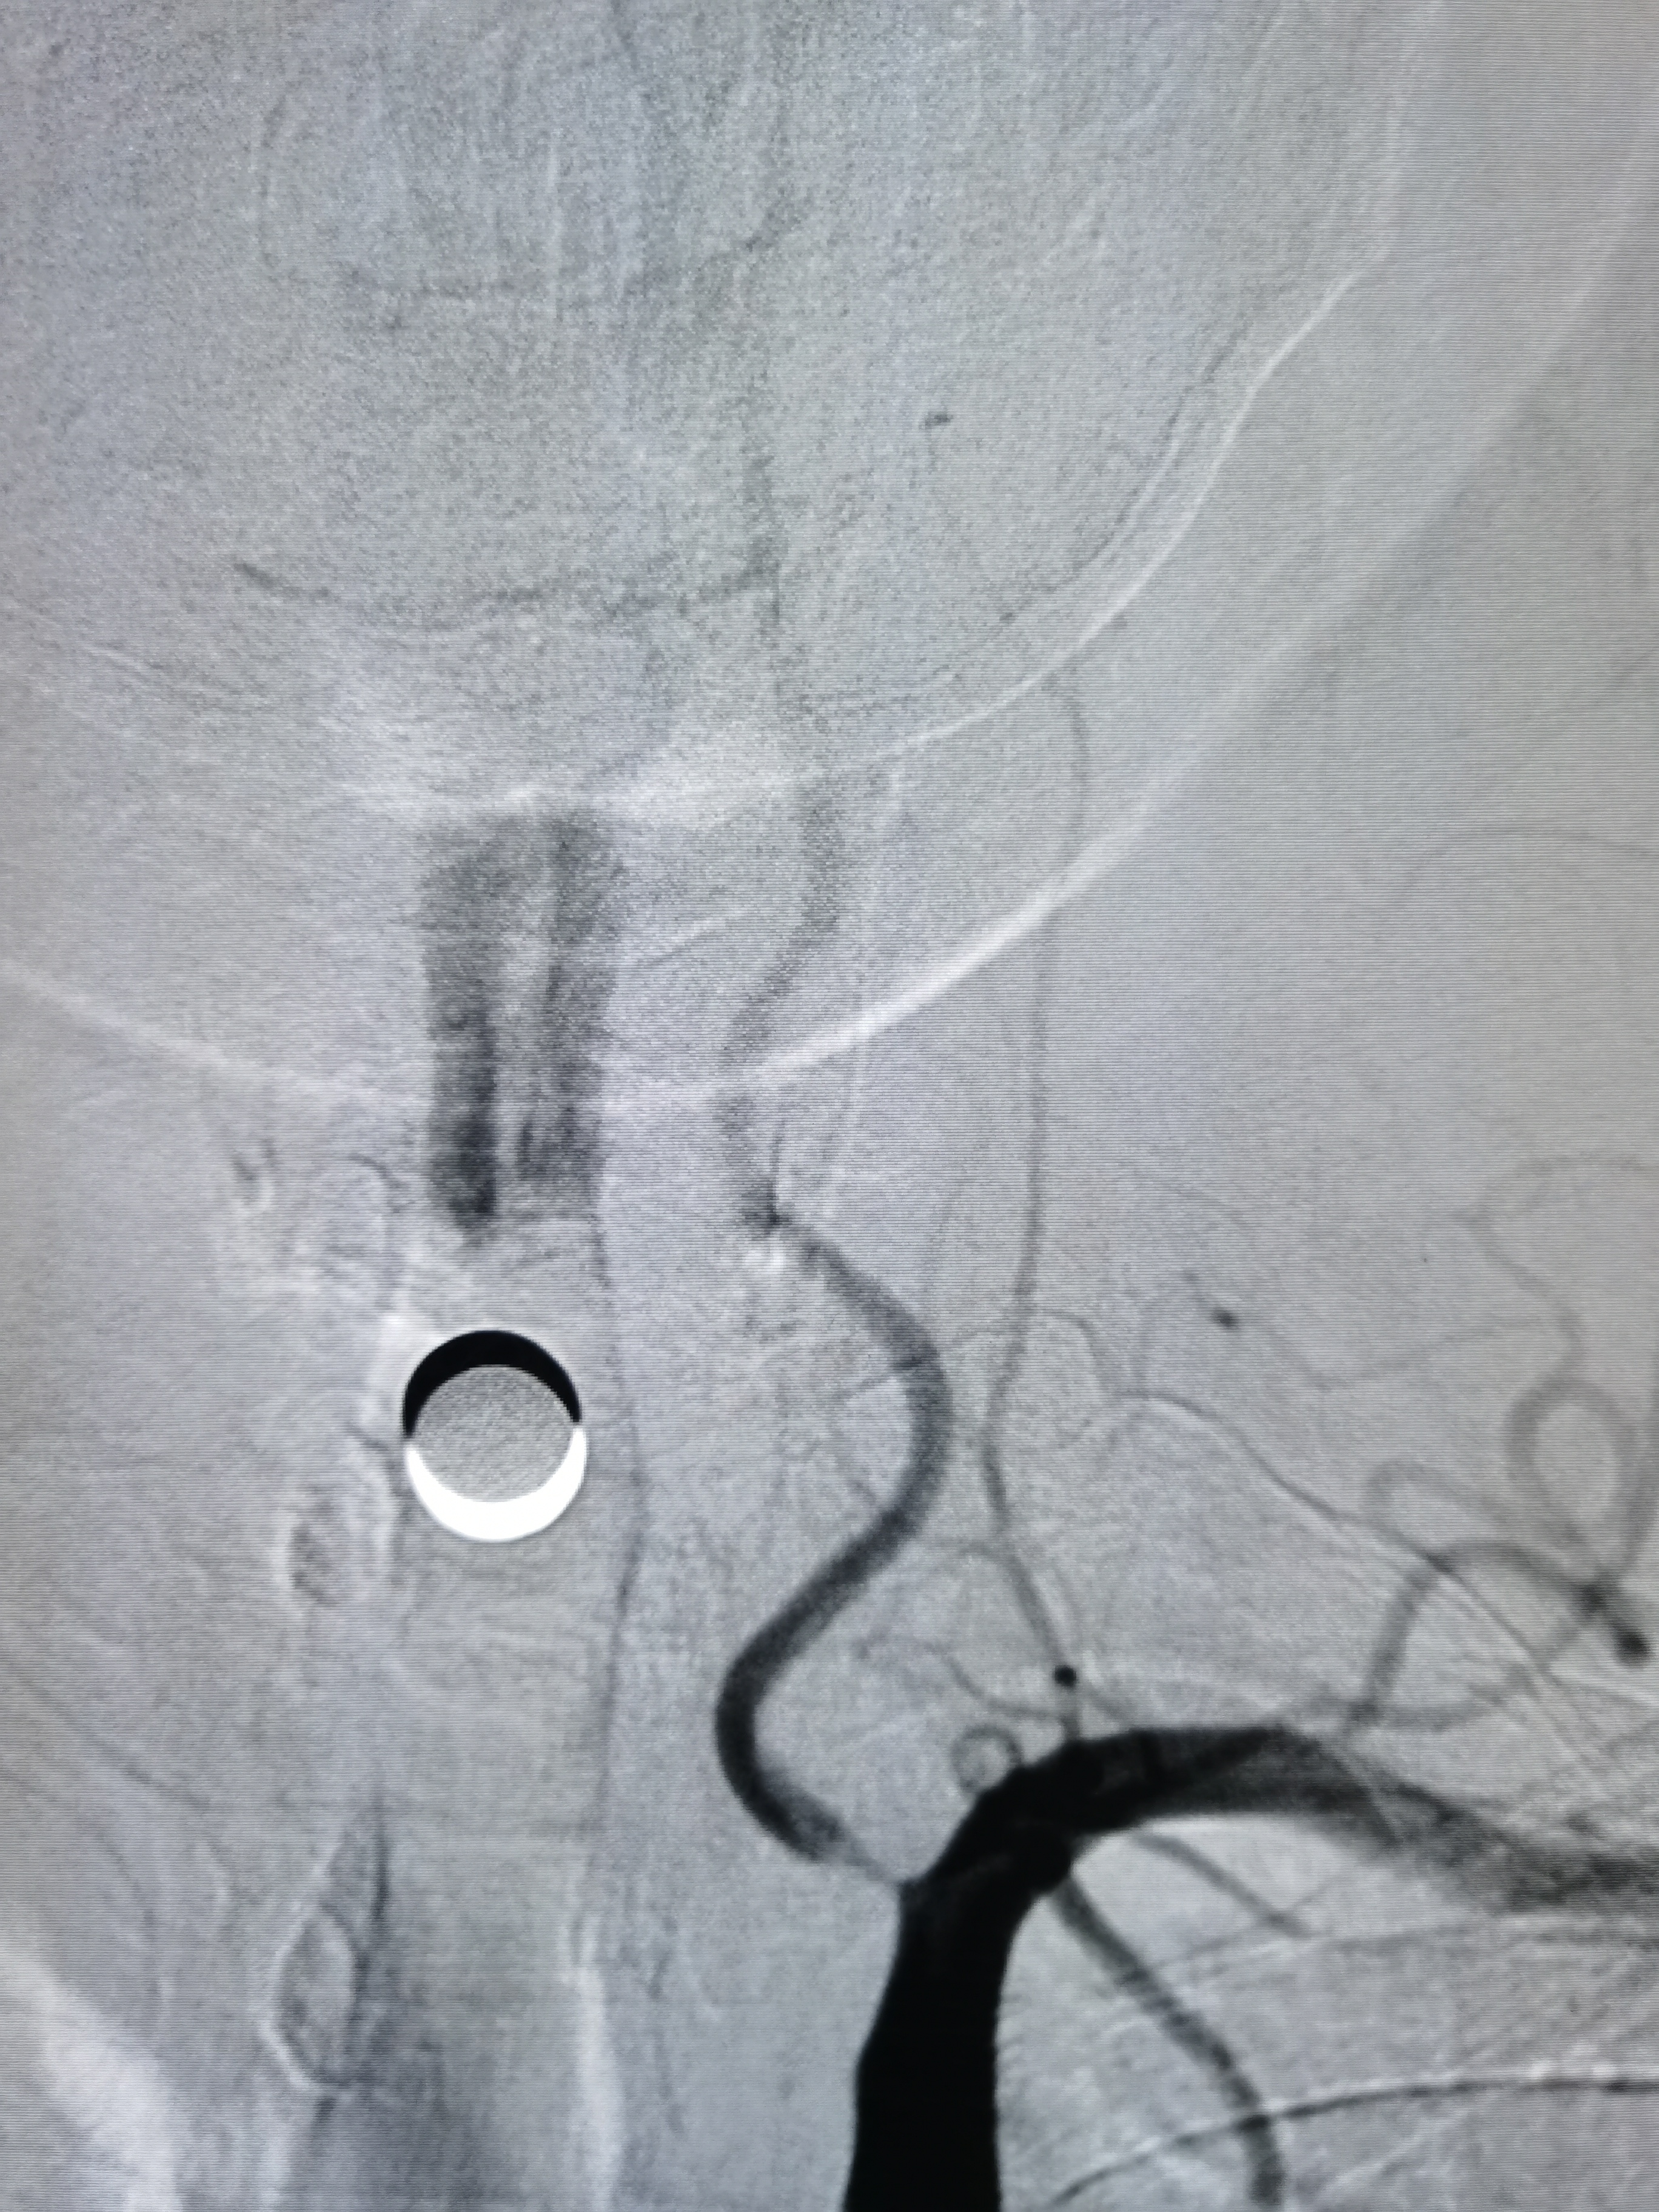

2、CTA证实左椎动脉起始部重度狭窄合并血栓,系责任血管,存在急性闭塞或残存血栓脱落至基底动脉风险,需积极处理。

3、手术过程中,先用小球囊扩张病变,观察血栓情况,及时应用支架全程覆盖血栓及病变部位,成形满意。